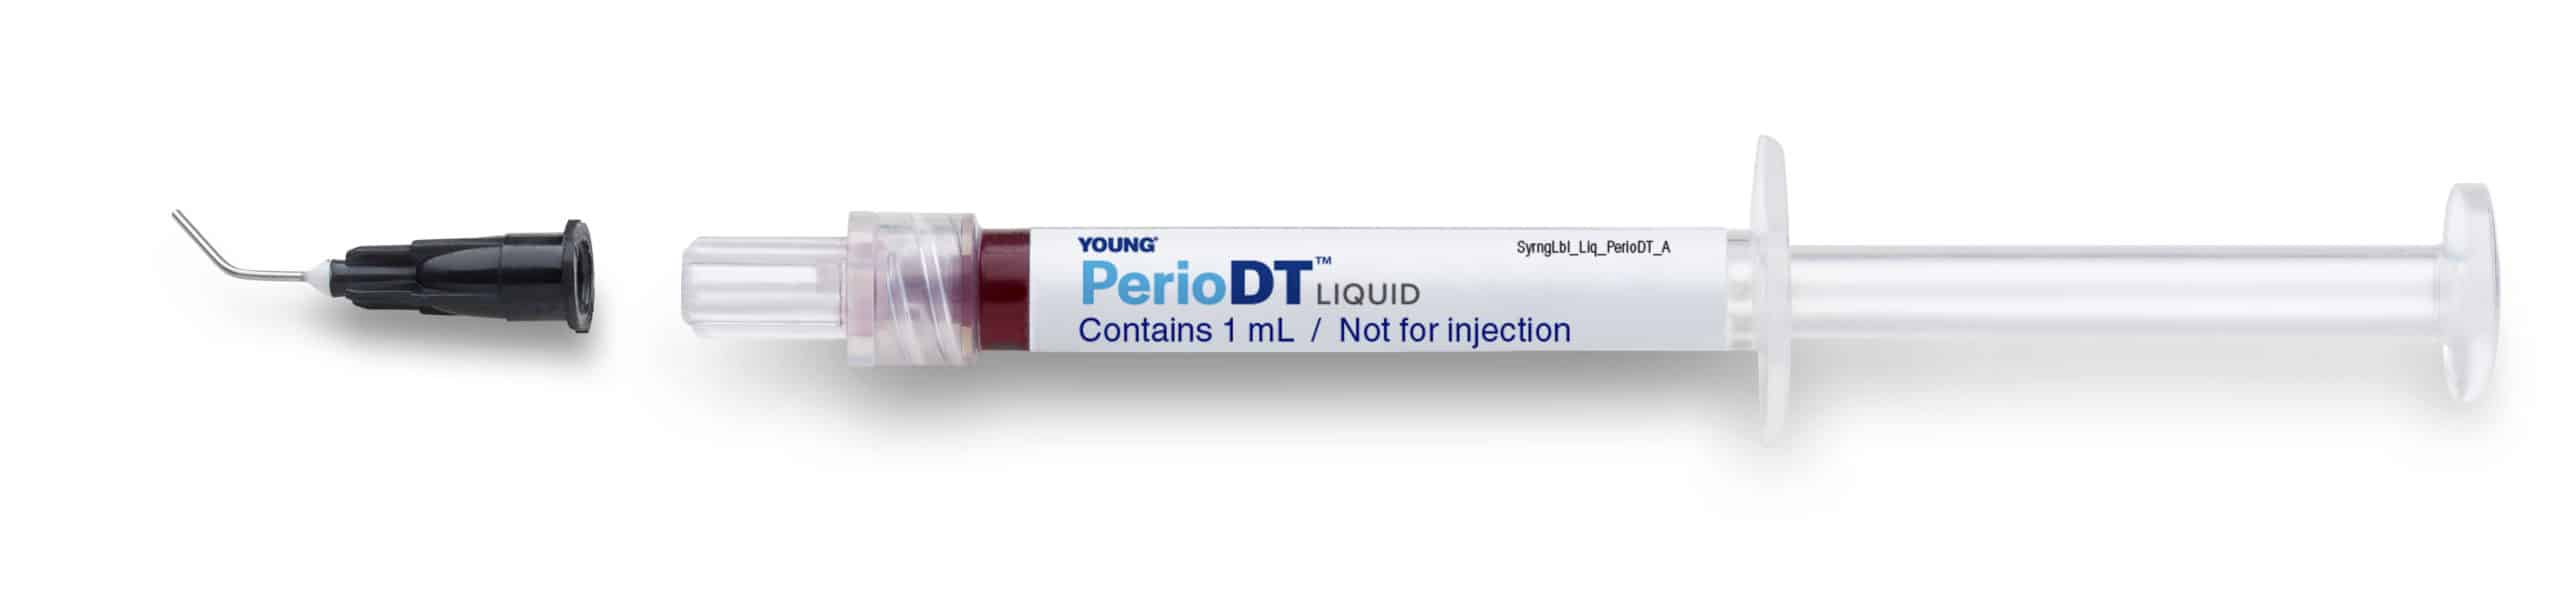

Young PerioDT with Dessication Technology

PerioDT Biofilm Debridement Sulfonated Phenolics

How does PerioDT work? The action of PerioDT is based upon the simple fast-acting principle of Desiccation Technology (DT). Desiccation is a simple physical process that removes water from the combination of infectious microbial material, dead cellular debris (necrotic material) and other macromolecules found around tooth and prosthetic surfaces in the oral cavity. This process occurs less than one minute after contact with those materials. Benefits:- Desiccation of dental plaque, calculus and biofilm present in periodontal pockets and surrounding tooth surfaces

- Two viscosity choices, liquid and gel

- Easy to use delivery system

- One syringe can complete a full arch

- Red color to show where it has been placed

PerioDT Product Profile (English) PerioDT Application (English) PerioDT Product Profile (French) PerioDT Application (French) PerioDT SDS (English)SKU:

PerioDT